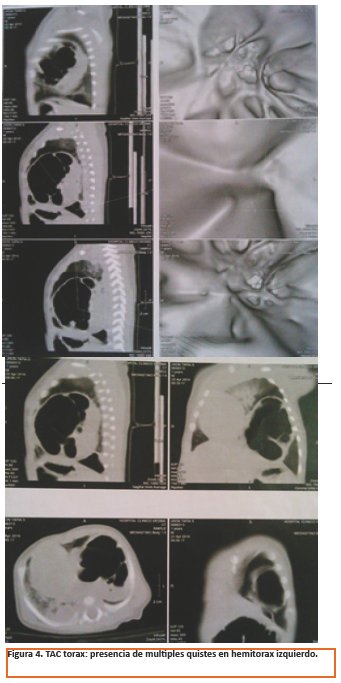

Entre las cusas puede jugar papel importante la anoxia neonatal y las maniobras de reanimación del recién nacido. Estudio de casos publicados sobre enfisema lobar, informan estos anteascendente y transverso, adecuado calibre de todo el marco colónico. Se descarta Hernia diafragmática y se solicita Tomografía axial computarizada.(Figura 4)

Donde se confirma la presencia de múltiples quistes en campo pulmonar izquierdo.

La TAC de tórax confirma lo anterior y demuestra la obstrucción bronquial, descartando hernia diafragmática.